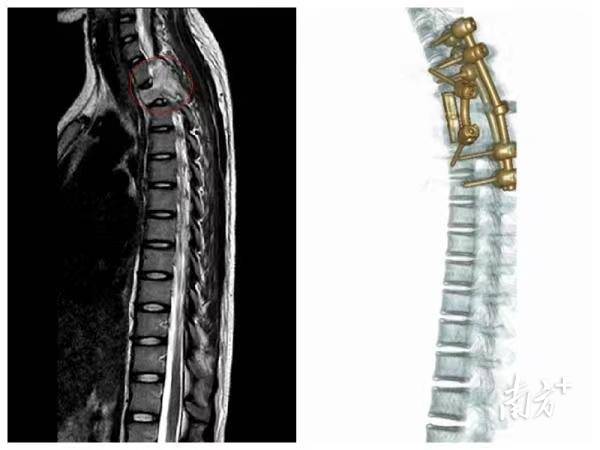

南医三院骨肿瘤科主任李浩淼查看小麦病历资料,将其收入院治疗,检查显示肿瘤压迫上位胸椎,属于治疗困难的颈胸椎交界区,手术比较棘手。肿瘤包裹着脊髓意味着分离二者时必须非常精准,能够操作的空间非常狭窄,稍有不慎就可能造成永久瘫痪。且无法正常看到椎动脉,术中医生需要凭借临床经验精准避雷,步步为营,挑战巨大。

在排除诸多困难后,医生为小麦制定了胸椎体及附件肿瘤整块切除(En-bloc)的手术方案,由于肿瘤呈330度环形包绕脊髓,周围又毗邻重要血管脏器,要完整切除肿瘤,同时保全脊髓和重要器官,难度巨大。

3D打印重建脊柱

11月8日下午,李浩淼主任主刀,为小麦手术,手术室外小麦父母席地而坐焦急等待。从下午三点到第二天凌晨一点,手术顺利完成,肿瘤被完整切除,并植入3D打印人工椎体进行稳固脊柱重建。当小麦妈妈见到从手术室出来的李浩淼时,忍不住抽泣起来。

全脊椎切除和脊椎次全切除手术都存在术中出血多、手术步骤复杂、手术风险大、局部重建困难等多个技术难点。李浩淼主任表示,南医三院是华南最早成熟开展脊柱肿瘤整块切除的医院之一,也是广东省最早使用3D打印人工椎体进行脊柱重建的单位,在复杂脊柱肿瘤的外科治疗方面积累了丰富的临床经验。